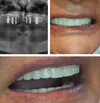

Zirconium Applications

Implant Treatment

Porcelain Applications